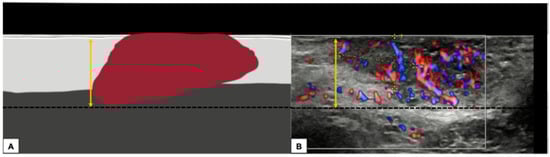

- Measurement from the adjacent most superficial dermal papilla to the deepest point of invasion

- Measurement from the basement membrane of the deepest adjacent dysplastic (tumor-free) rete ridge to the deepest point of invasion, which should be the technique of choice. Because epidermal ridges cannot be distinguished on ultrasonography, our suggestion is to take the lower hyperechogenic line of the epidermal layer as a reference (Figure 10).